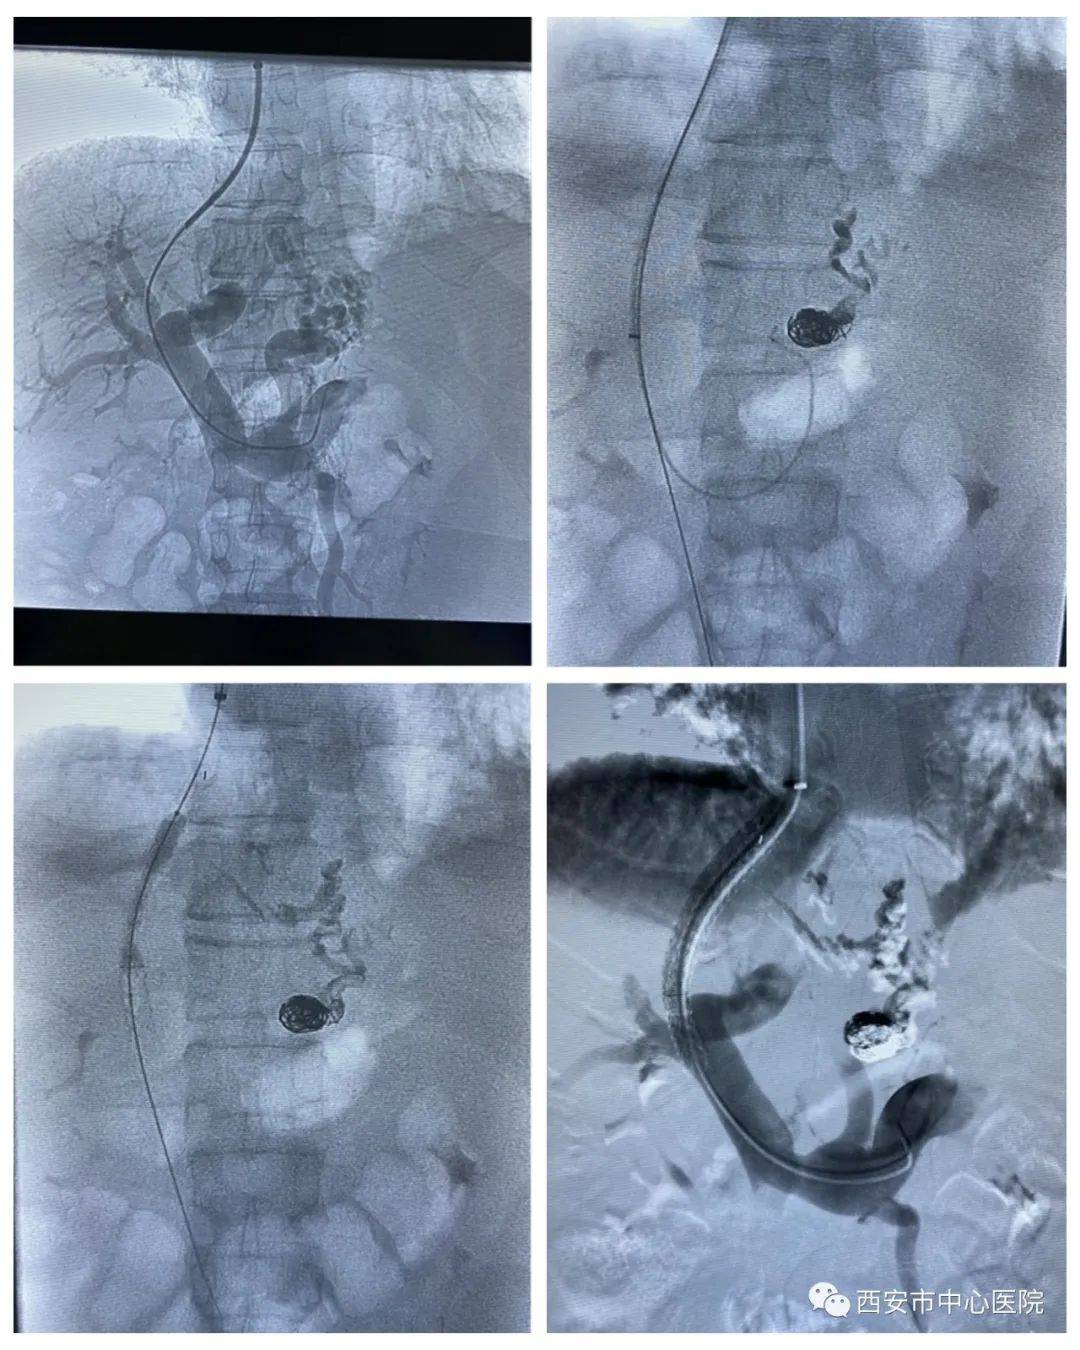

穿刺成功后造影→封堵曲张静脉→

置入支架→术后造影

而这小小的针眼背后 , 其实有着不一样的故事 , 术中 , 医生需要经过患者颈内静脉穿刺 , 通过上腔静脉、右心房及下腔静脉 , 进入肝静脉内 , 再使用穿刺针精确制导穿刺进入门静脉 , 封堵患者的曲张静脉 , 并在肝内放入支架连通门静脉及肝静脉 , 降低门静脉压力 , 手术难度丝毫不亚于在秦岭山中打通隧道 。 正是如此 , 这一手术也是消化介入领域难度最高的四级手术 , 而西安市中心医院是目前市级医院中唯一能开展此类手术的医院 。